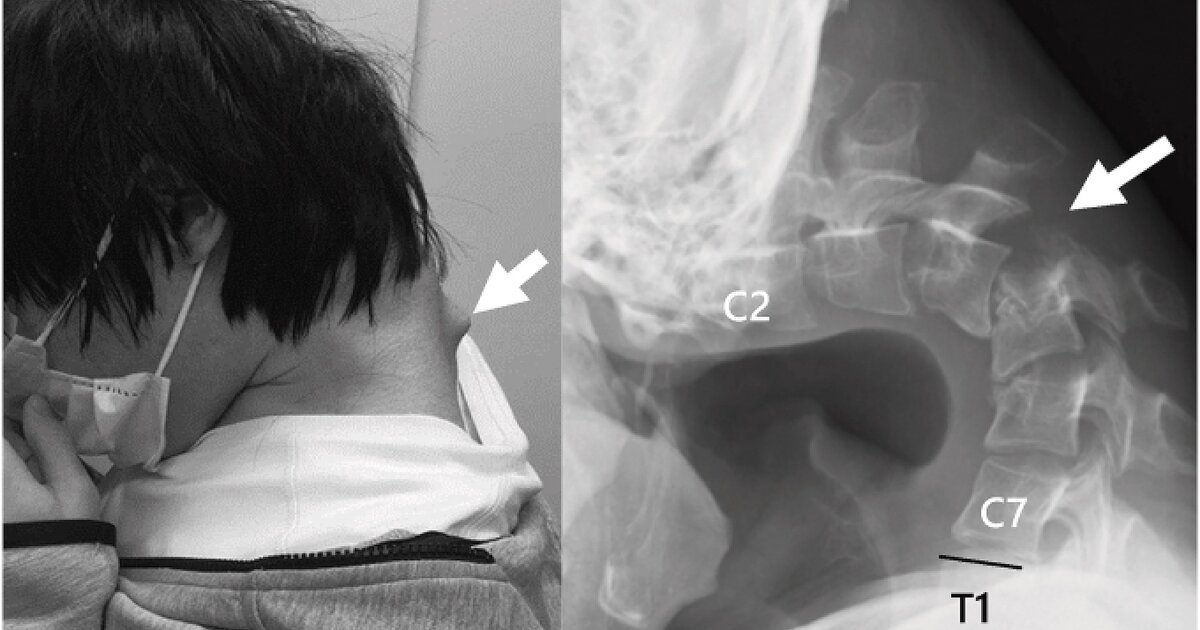

Αποτέλεσμα αυτής της στάσης ήταν να αναπτυχθεί ένα εξόγκωμα στον αυχένα, ενώ ο ίδιος έχασε πλήρως την ικανότητα να σηκώνει το κεφάλι του. Η κάμψη ήταν τόσο προχωρημένη, που το πηγούνι του ακουμπούσε μόνιμα στο στήθος.

Το 2023, ο νεαρός άρχισε να υποφέρει από αφόρητο πόνο στον αυχένα και δυσκολία στην κατάποση, η οποία προκάλεσε ταχεία απώλεια βάρους. Οι ιατρικές εξετάσεις αποκάλυψαν έντονη παραμόρφωση των αυχενικών σπονδύλων, καθώς και βλάβη στην ανώτερη σπονδυλική στήλη – συνέπειες της μακροχρόνιας καταπόνησης και υπερέκτασης των μυών του αυχένα.